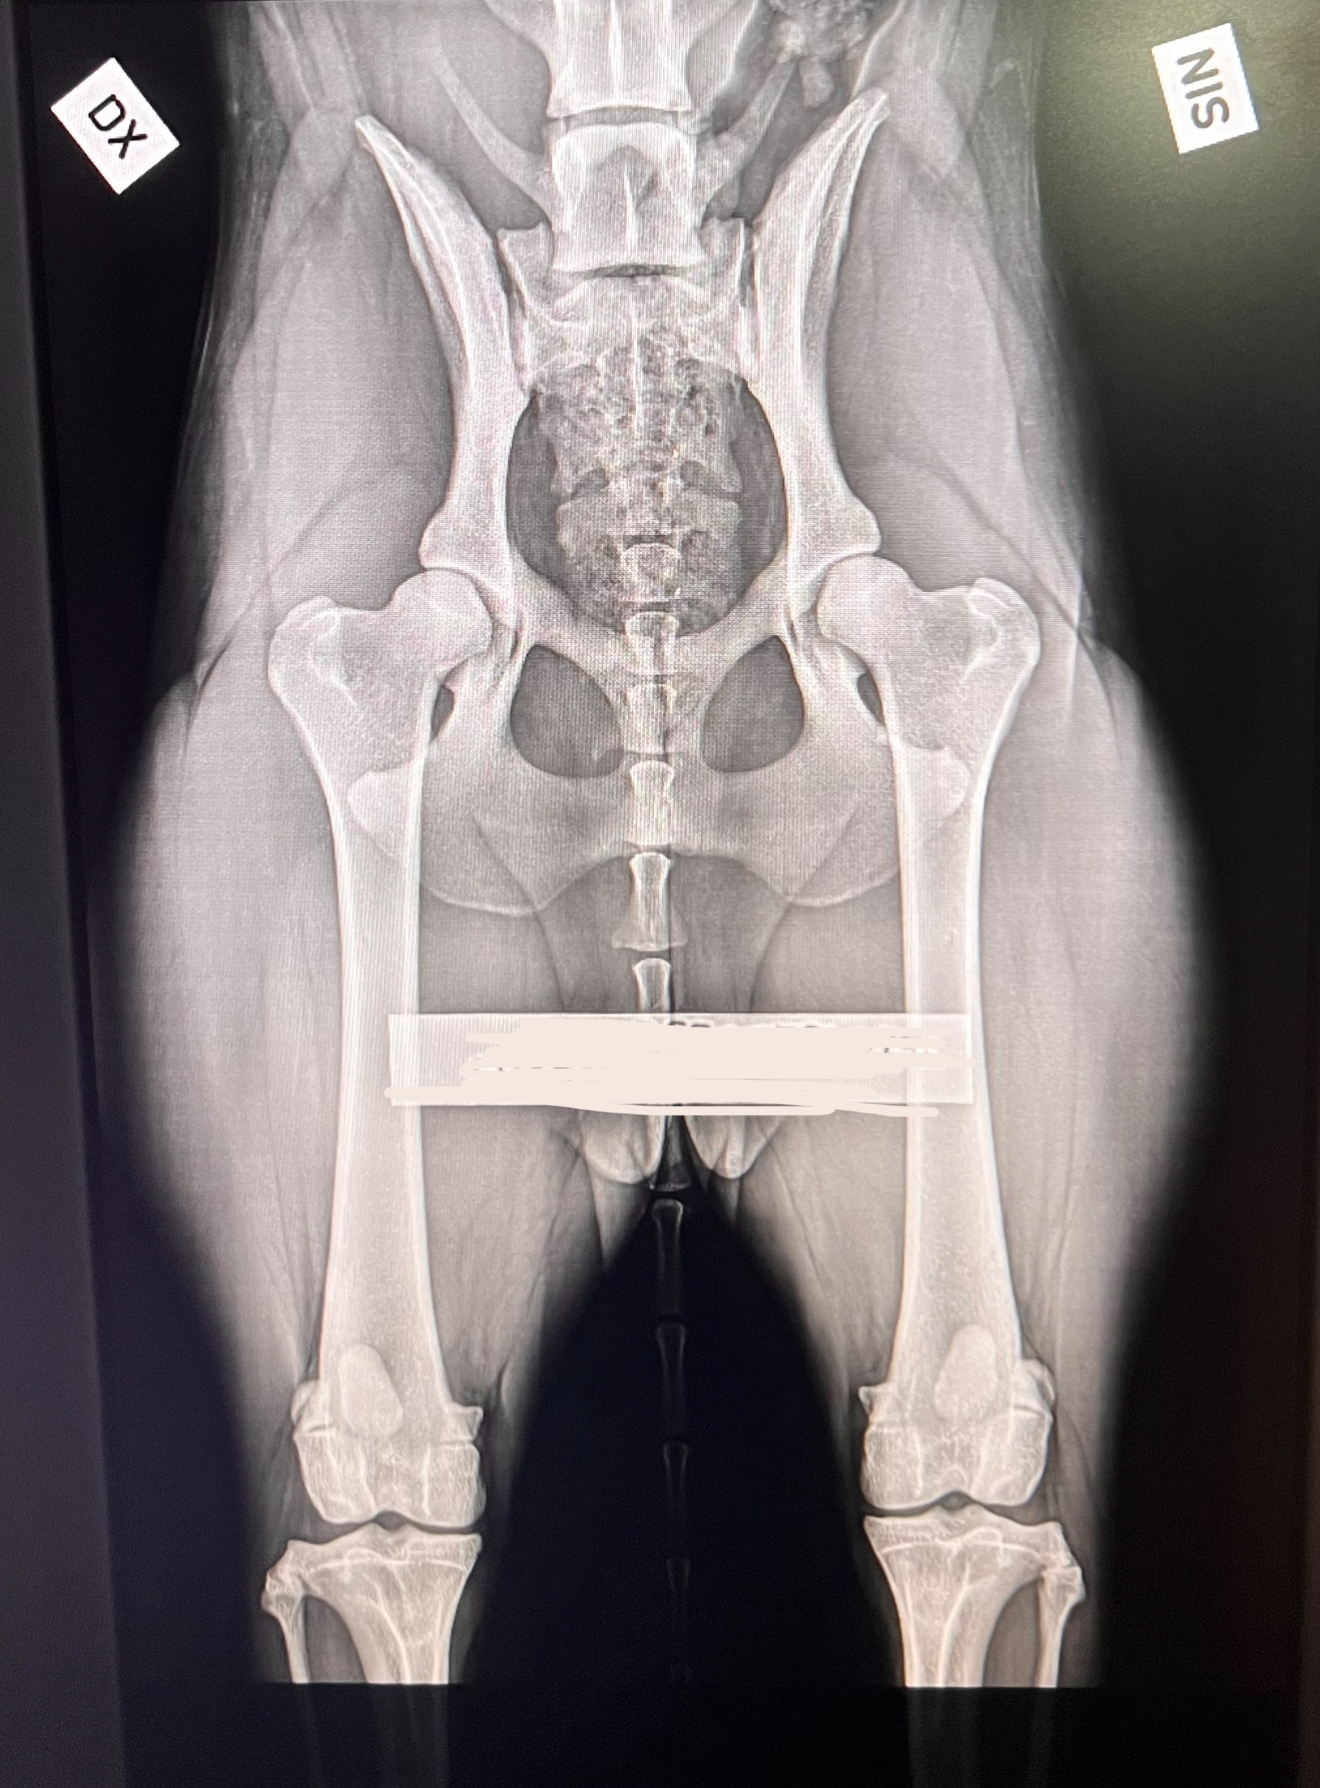

Vi röntgar enligt SKK:s riktlinjer med hög noggrannhet för en sund avel och friska hundar.

Och ja – vi röntgar även katter! 🐱 På sista bilden ser ni en HD-bild på en Maine Coon.